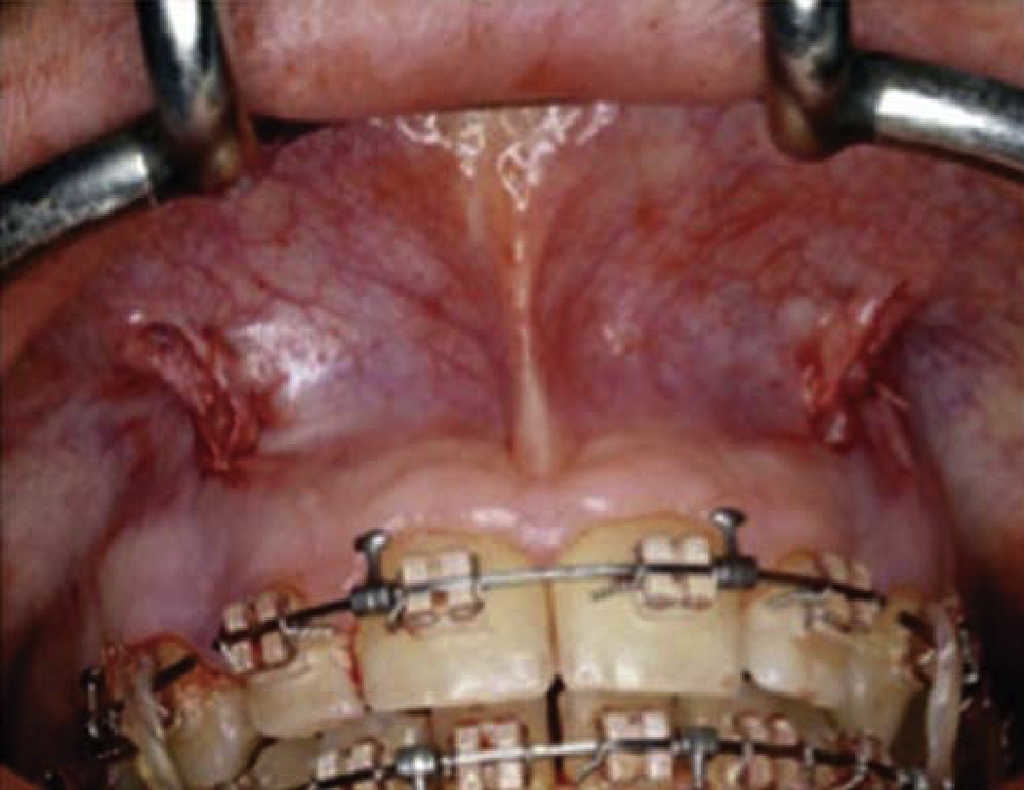

This technique, proposed in 2001 by the orthodontist and periodontist Wilcko brothers is executed in three surgical phases.4

First phase: selective alveolar decortization was conducted, and a total thickness (muco-periosteal) flap was raised.2 Vertical corticotomies were executed in inter-radicular spaces, (vestibular/lingual/palatal) with a number 1 round burr, preserving a distance of 2-3 mm to the osseous crest and exceeding by 2 mm the dental apex.2 According to each case, vertical corticotomies were linked to semi-circular corticotomies in the upper or lower portion of the apex (Figure 8).4 After this, 0.5 mm deep perforations were undertaken on the root of the tooth with a round burr. These perforations were limited to vestibular and lingual cortical bone and had the aim of providing maximum bleeding (Figure 9).4 This technique recommends to locate perforations in the thickest areas of cortical bone, following dental root morphology.4

Figure 8 Link of inter-radicular vertical corticotomies with semi-circular cortcotomies at the apical third.

Second phase: consists on following alveolar increase procedures by placing bone graft material. Decalcified matrixes stimulate osteoblastic activity (Figure 10), thus, after procedure, alveolar volume increase is achieved. Flaps are sutured with 4-0 silk or 5-0 Gortex; sutures are removed 2 or 3 weeks later, depending on post-surgical assessment.4

Third phase: It consists on application of orthodontics forces every two weeks. It is recommended to place appliances one week before corticotomy, although they can be placed 2 to 3 weeks after surgery so as to facilitate surgical procedure (Figure 11). Orthodontic activations can be conducted every two weeks. Movement rate achieved with this technique is 1-2 mm per week, in comparison with the single monthly millimeter achieved with a conventional orthodontic treatment.4

Advantages of this technique are the following: excellent visibility to execute procedure, possibility of achieving corticotomies with electrical scalpel or burr,2 4 treatment time decrease,4 faster dental movements, lacking associated root resorption or pulp lesion in teeth subjected to dental movement13 accelerated canine retraction after premolar extraction.13 14 Execution of alveolar increase and remodeling (covering with bone graft) improves gingival esthetics.4 Disadvantages of this technique are prolonged surgical time as well as tissue inflammation proportional to treatment, ecchymosis and pain.2